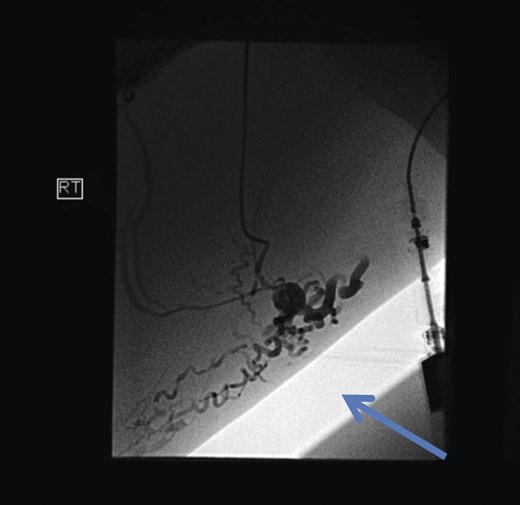

The superficial external pudendal vein was embolized with 1% sodium tetradecyl sulphate and then coiled through a contralateral puncture under fluoroscopic guidance (Figs 3 and 4). The procedure went uneventfully with successful obliteration of the communicating thigh veins to vulval varices (Fig. 5) and the patient was discharged home the same day.

Post-procedure fluoroscopy showing successful obliteration of communication of thigh veins to vulval varices (blue arrow).